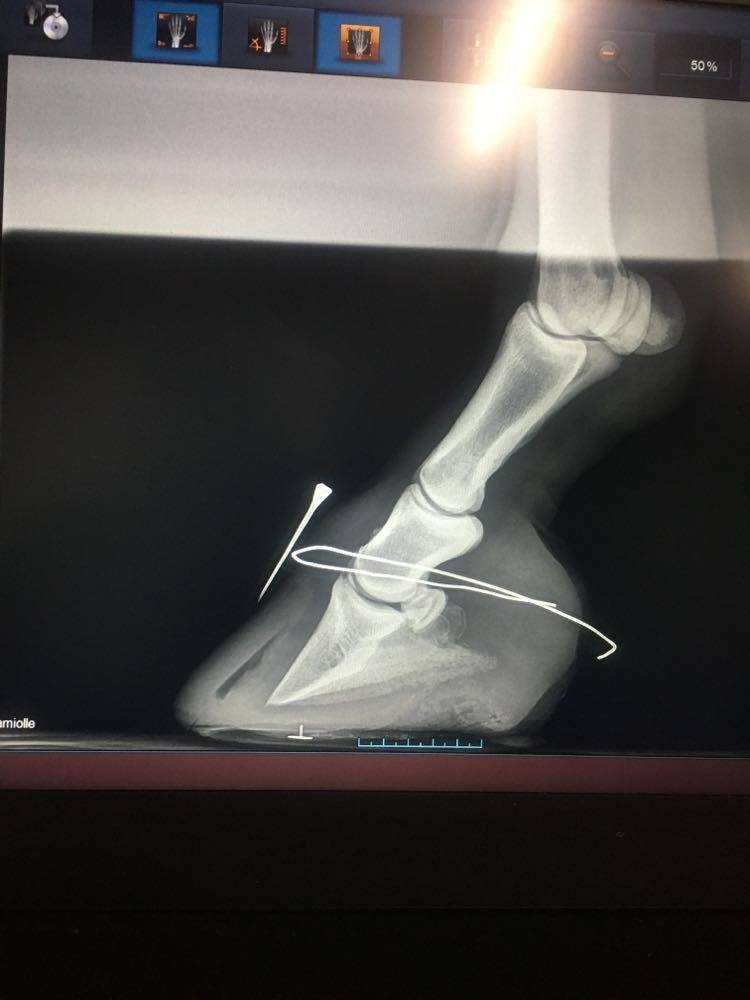

DéconnectéDire merci | muesli08 Au sujet des radios, oui je les ai vues. Est ce que vous pourriez poster toutes les radios et peut être obtenir de votre vétérinaire les radios sans notation écrite dessus car elles masquent une partie des radios, en particulier elles empêchent de voir clairement l'épaisseur de la sole? Certainement qu'en discutant avec Remco, il vous a précisé les points importants du parage de réalignement, dont le fait, dès le premier parage de raccourcir la pince de façon à ramener le point de bascule à sa vraie position c'est à dire juste devant la vraie ligne blanche ( pour corriger l'angle dorsal ) et de faire un chanfrein en pince et sur tout le pourtour du pied ( pour supprimer les forces de séparation exercées sur les lamelles affaiblies/la paroi du sabot par le poids du cheval et permettre à la nouvelle paroi qui pousse à partir de la bande coronaire de pousser dans le bon angle parallèle à la face dorsale de P3). Les talons doivent être abaissés pour restaurer un angle palmaire autour de 5 degrés. Je ne vois pas bien à cause des inscriptions sur la radio mais la sole ne semble pas très épaisse sous la pointe de P3; il est important que la sole se développe à cet endroit et donc les talons doivent être abaissés qu'à partir de la hauteur de la fourchette, ce qui va laisser le pied en 2 plans au niveau de sa surface solaire, le temps que la sole se développe à l'avant du pied mais ce n'est pas grave si les piesds sont bien soutenus dans des boots avec des semelles épaisses à l'intérieur. J'essaie de vous faire des tracés sur les radios pour que cela soit plus clair si vous le souhaitez et de vous envoyer des infographies sur le sujet. |

| Dire merci | ![]() voilà j'ai réussi et oui j'ai lu sur la page TLS Elle a déjà eu un premier parage avant radio où les talons ont été baissé une bonne fois (je pense qu'il avait retiré plus d'1/2 cm, les talons étaient à 25mmm, depuis je l'ai descendue à 20mm jusqu'au plan de la sole, avec chanfrein et la pince avait bien été reprise également pour retirer la pression lamellaire, c'est d'ailleurs après ce premier parage à J11 qu'elle s'est sentie beaucoup mieux ! |

| Dire merci | bon je viens donner des nouvelles ! radios de mercredi : ![]() ![]() la rotation es déjà bien corrigée là il me reste à rétablir un point de break over parfait : surtout sur base de la punaise à l'apex qui me permettra de couper pile poil où il faut. ça repousse , lentement ne pince, plus vite en talons ce qui donne de précieuses indications : que je dois surveiller la hauteur de talons chaque semaine et les garder à hauteur de la sole en permanence. Muesli n'est plus du tout sensible sur sol souple !!! Elle garde tout de même ses chaussures et semelles en permanence : vu la poche de gaz , je dois me méfier , la laisser marcher sans soutien pourrait accentuer la bascule. je pare les prochains jours (j'attends les mark ups, j'ai bien ma petite idée, mais je ne peux me permettre d'être approximative. ) édit car j'oublie toujours de refermer les parenthèses que j'ouvre et aussi pour vous dire : regardez comme la sole s'est épaissie sous la pointe de p3 en 3 semaines !! Message édité le 06/12/20 à 19:33 |

En ligneDire merci | la sold a bien repris c’est top et la deuxième radio l’alignement est pas mal du tout tu as vraiment de quoi reprendre en talon et en pince en plus. les poches de gaz vont partir avec la reprise en pince sur tes parages c’est douloureux donc fais gaffe à bien garder le pied dans des boots . maintenant c’est surtout le pied de la première radio à travailler pour reprendre l’alignement mais c’est vraiment nettement mieux |